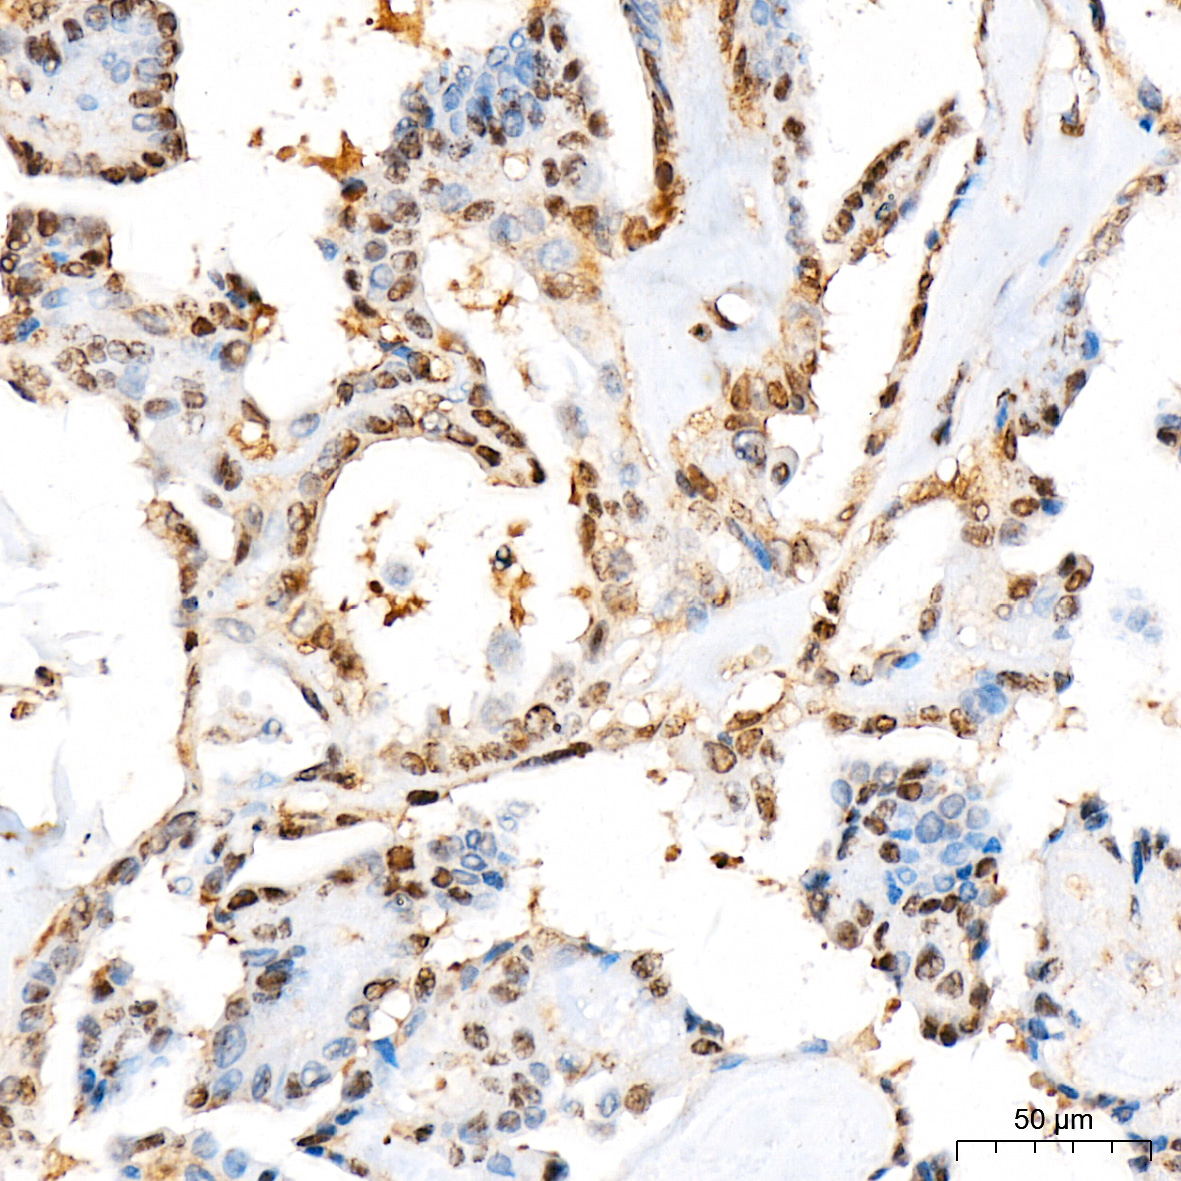

| Immunohistochemistry analysis of paraffin-embedded Human thyroid cancer tissue using [KO Validated] STAT3 Rabbit mAb (A19566) at a dilution of 1:200 (40x lens). High pressure antigen retrieval was performed with 0.01 M citrate buffer (pH 6.0) prior to IHC staining. |